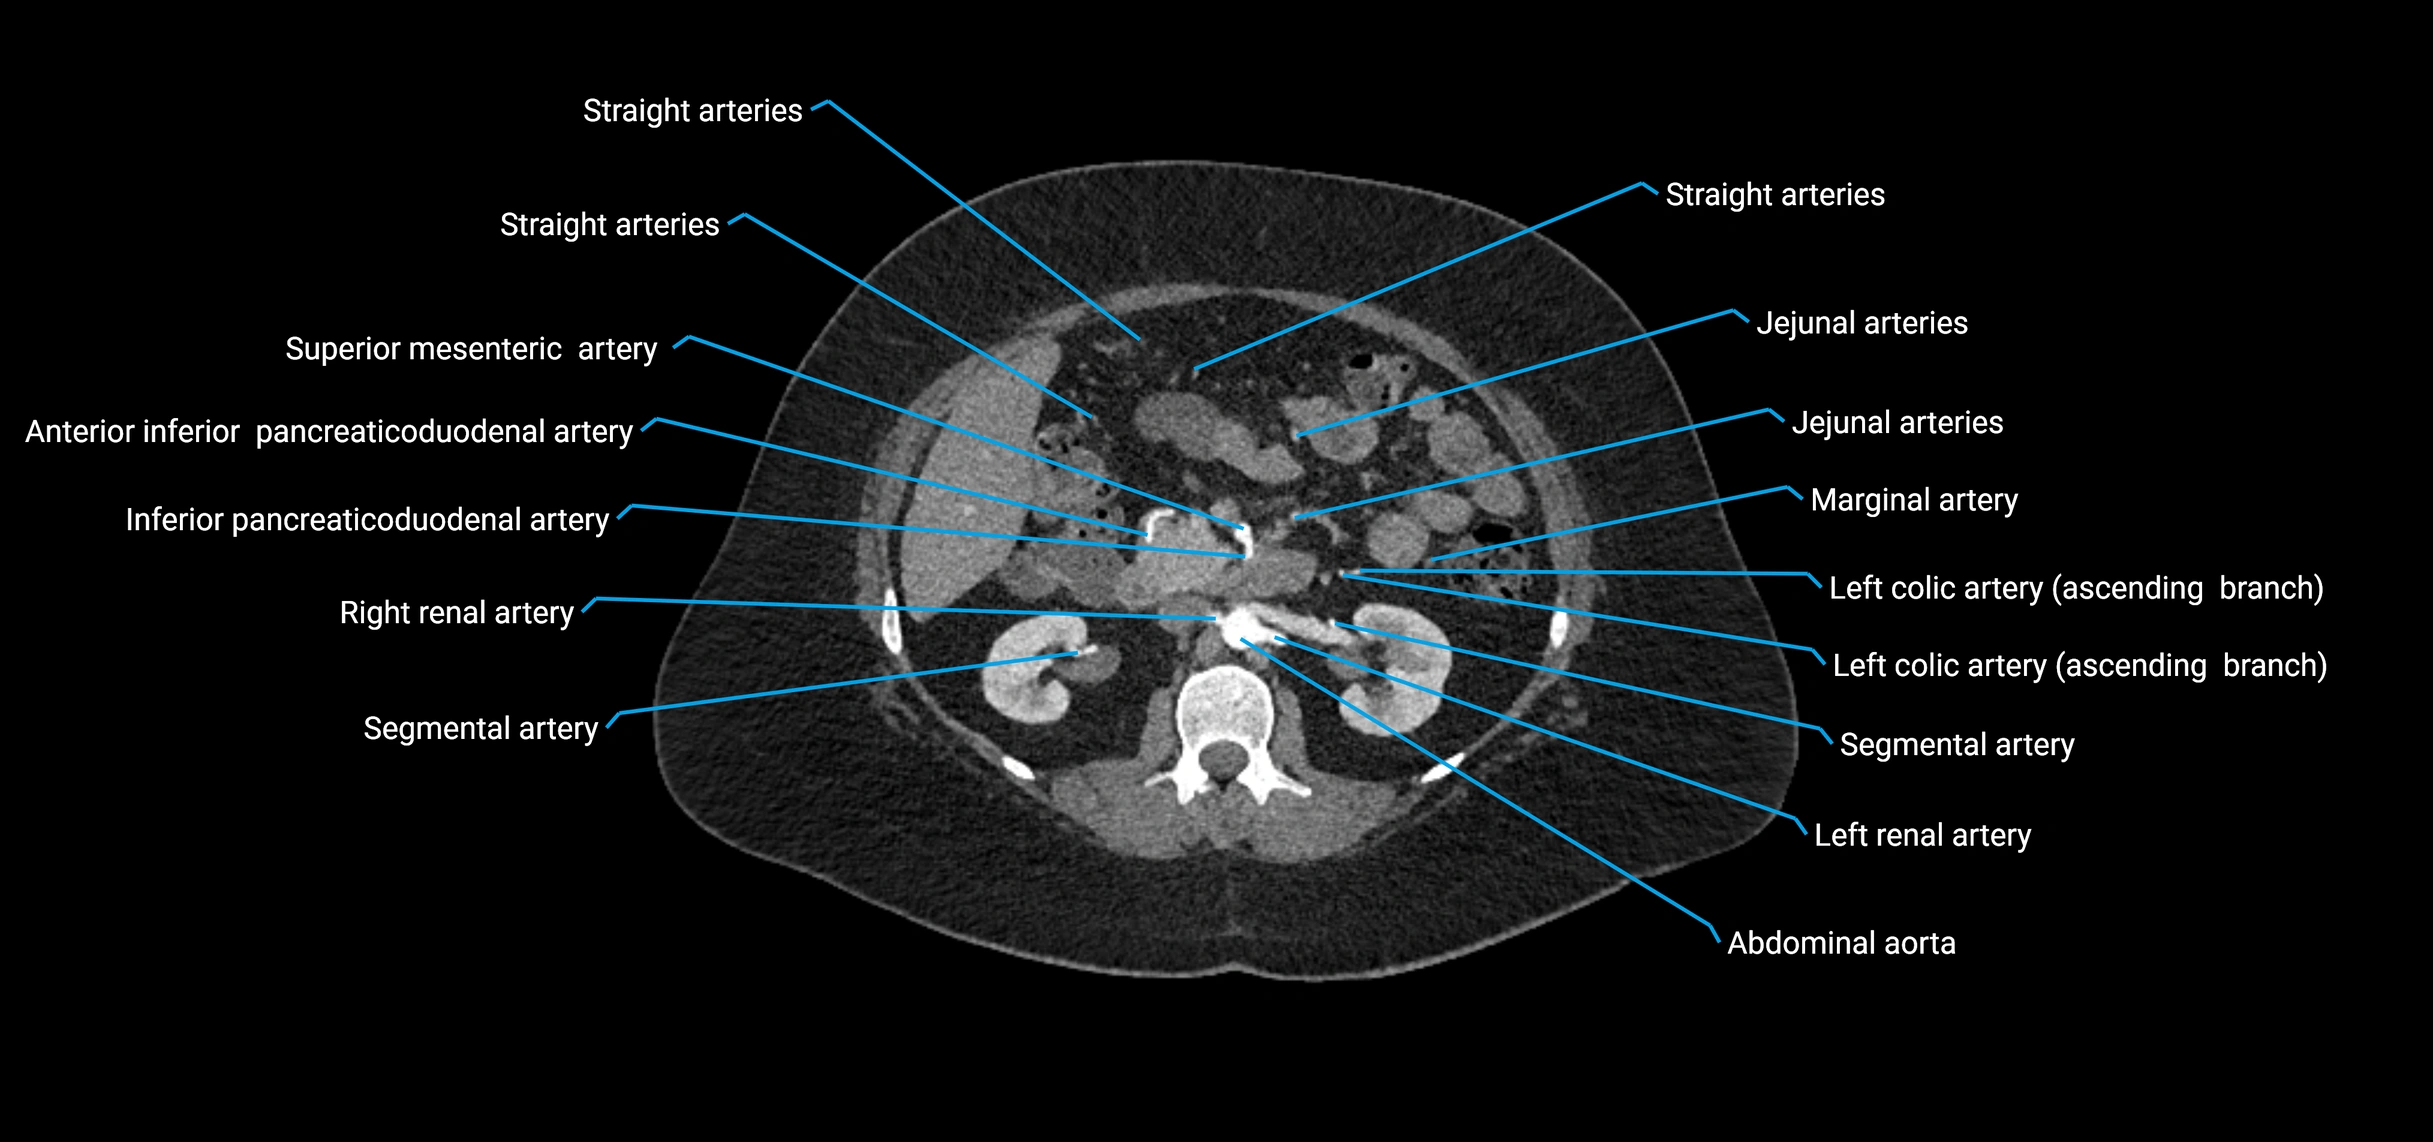

Contrast-enhanced CT (CTA):

• Gold standard for abdominal aortic imaging

• Provides excellent detail of lumen, wall, aneurysm, thrombus, and branch vessels

• Multiplanar and 3D reconstructions help in aneurysm measurement, stent graft planning, and dissection evaluation